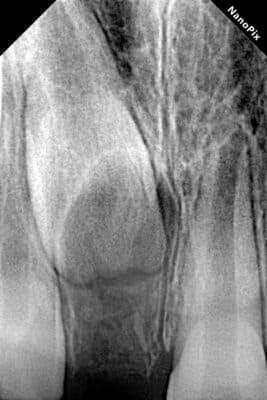

Видалення надкомплектних зубів. Бродик Богдан.

Надкомплектні зуби — це той випадок, коли зубів у зубному ряду є більше, ніж задумано. У такому випадку вони заважають повноцінному прорізуванню основних зубів та створюють ортодонтичні проблеми. Вихід у даному випадку — видалення надкомплектних зубів з подальшим ортодонтичним лікуванням. Завдяки злагодженій роботі з анестезіологічною командою проведене делікатне видалення надкомплектного зуба, ушивання рани, і тепер юна пацієнтка готова до того, аби її посмішка формувалась належним чином.